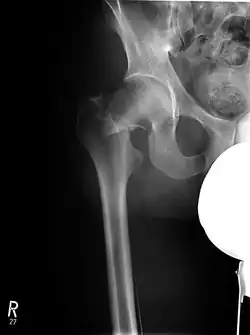

Außenrotiertes und verkürztes Bein bei Schenkelhalsfraktur rechts

Typisch – vor allem für die mediale Schenkelhalsfraktur – sind das außenrotierte und verkürzte Bein auf der betroffenen Seite. Hinzu kommen meist starke Schmerzen in der Leiste und Klopfschmerzen über dem großen Rollhügel (Trochanter major s. o.). Eingestauchte und nicht dislozierte Frakturen können symptomlos verlaufen. In diesen Fällen werden die dumpfen Schmerzen nach Unfall-/Sturzereignis oft für eine Prellung gehalten. Patienten mit solchen Frakturen kommen nicht selten noch zu Fuß zum Arzt oder in die Klinik und geben Schmerzen beim Laufen an. Frakturen mit starker Dislokation, beispielsweise bei total abgerutschtem Femurkopf, verursachen starke Schmerzen und kommen als Notfall in die Klinik. Schenkelhalsfrakturen mit Dislokation bedürfen meist keiner langen Diagnostik, der Befund fällt sprichwörtlich ins Auge. Im Röntgenbild sind die typischen Stauchungszeichen oder, je nach Frakturtyp, eventuelle Dislokationen des Femurkopfes zu erkennen.